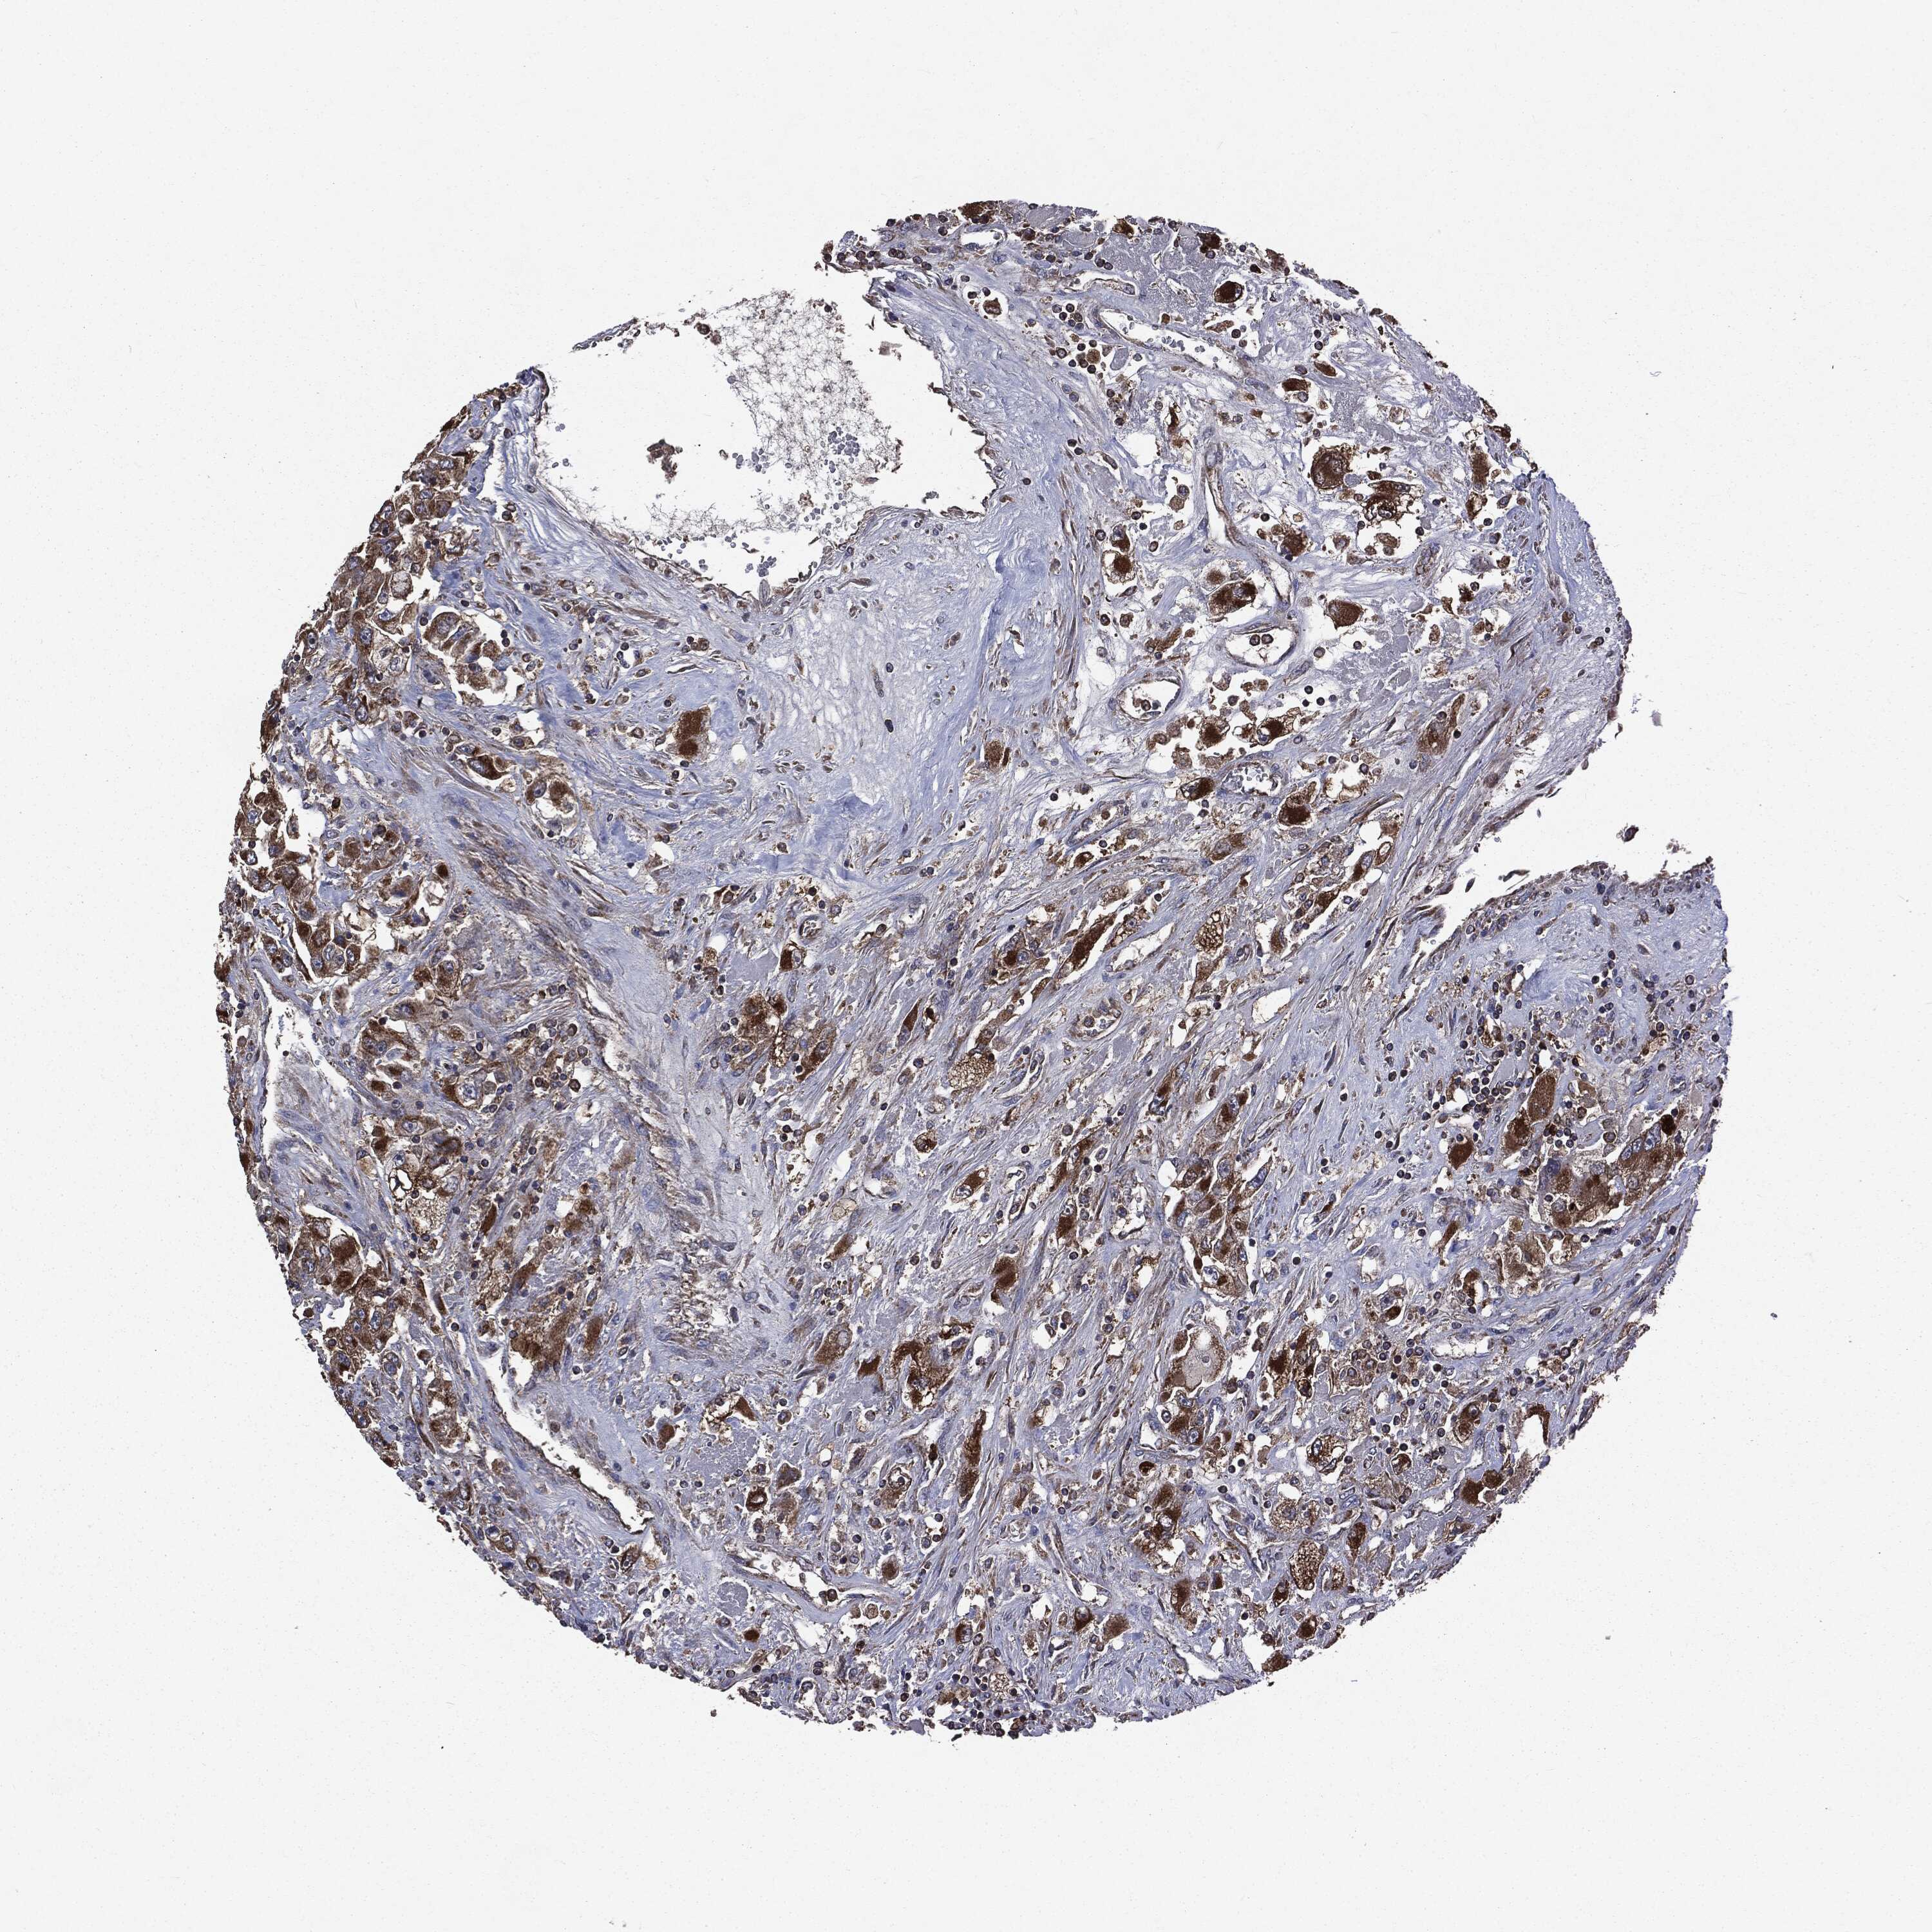

KIDNEY RENAL PAPILLARY CELL CARCINOMA (TCGA) - Interactive survival scatter ploti

The Survival Scatter plot shows the clinical status (i.e. dead or alive) for all individuals in the patient cohort, based on the same data that underlies the corresponding Kaplan-Meier plots. Patients that are alive at last time for follow-up are shown in blue and patients who have died during the study are shown in red.

The x-axis shows the expression levels (FPKM) of the investigated gene in the tumor tissue at the time of diagnosis. The y-axis shows the follow-up time after diagnosis (years). Both axes are complimented with kernel density curves demonstrating the data density over the axes. The top density plot shows the expression levels (FPKM) distribution among dead (red) and alive patients (blue). The right density plot shows the data density of the survived years of dead patients with high and low expression levels respectively, stratified using the cutoff indicated by the vertical dashed line through the Survival Scatter plot. This cutoff is automatically defined based on the FPKM cutoff that minimizes the p-score. The cutoff can be changed by dragging the vertical line or by entering a cutoff value in the square labeled "Current cut-off".

Under the Survival Scatter plot the p-score landscape (black curve; left axis) is shown together with dead median separation (red curve; right axis). Dead median separation is the difference in median mRNA expression between patients who have died with high and low expression, respectively. It is calculated as follows: median FPKM expression of dead patients with high expression - median FPKM expression of dead patients with low expression. This is intended to aid the user in visually exploring custom cutoffs and the associated p-scores and dead median separation.

Individual patient data is displayed and can be filtered by clicking on one or more of the category buttons on the top of the page. Categories describing expression level and patient information include: high, low, alive, dead, female, male and tumor stages. The scale of the x-axis can be toggled between linear and log-scale by clicking on the "x log" button. Mouse-over function shows TCGA ID, patient information and mRNA expression (FPKM) for each patient.

& Survival analysisi

Kaplan-Meier plots summarize results from analysis of correlation between mRNA expression level and patient survival. Patients were divided based on level of expression into one of the two groups "low" (under cut off) or "high" (over cut off). X-axis shows time for survival (years) and y-axis shows the probability of survival, where 1.0 corresponds to 100 percent.

MAPK6 is not prognostic in Kidney Renal Papillary Cell Carcinoma (TCGA)